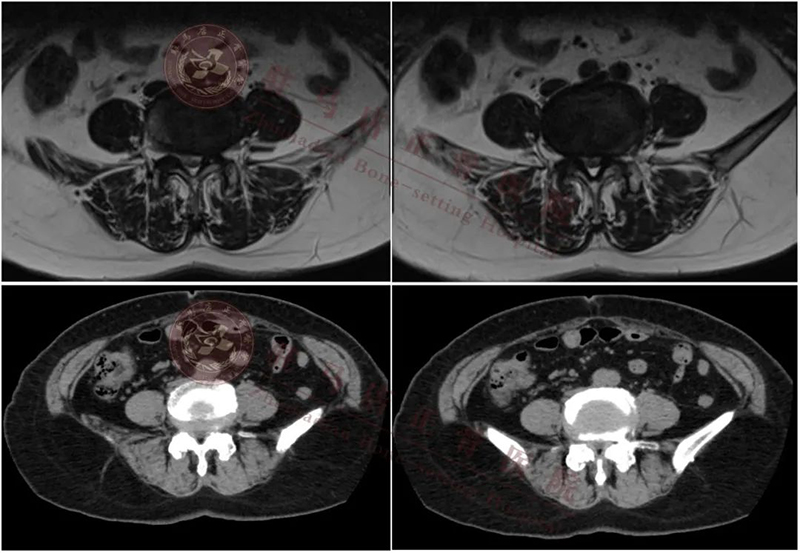

术中定位

镜下测量神经根距离

术中减压范围

植入cage

cage横打的位置

术中操作